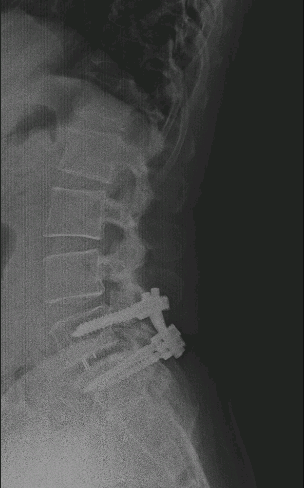

Paciente intervenido hace más de 3 años L5-S1 en otro centro que presenta recidiva de la clínica por la que se operó. En RX se evidencia ausencia de fusión.

Obsérvese la fractura del tornillo caudal como signo de ausencia de fusión.

Se realiza TLIF L5-S1 recolocando el tornillo de S1 en un trayecto más craneal.